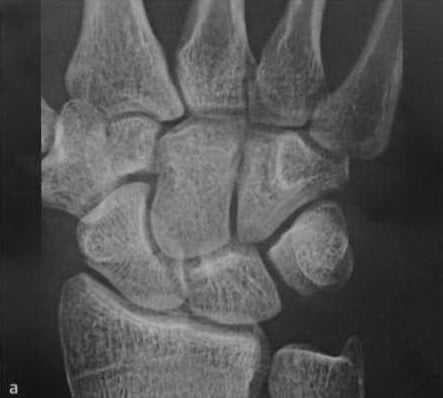

а, b Перелом ладьевидной кости (средняя треть), (а) Дополнительное наложение головчатой кости.

(b) Линия перелома лучше визуализируется при локтевом отведении и локтевом наклоне поверхности запястья.